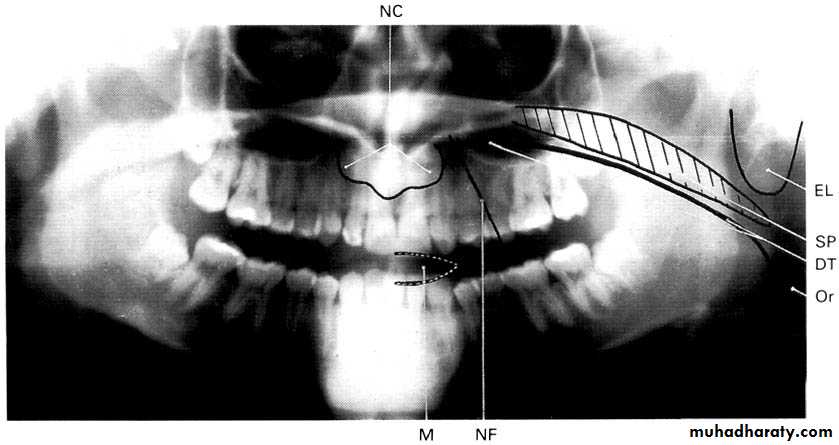

A dental panoramic tomograph showing the main real soft tissue and air shadows drawn in on

one side of the radiograph, NC — nasal cartilages, EL — ear lobe, SP — soft palate,

DT — dorsum of tongue, Or — oropharnyx, NF — naso-labial fold, M — mouth.